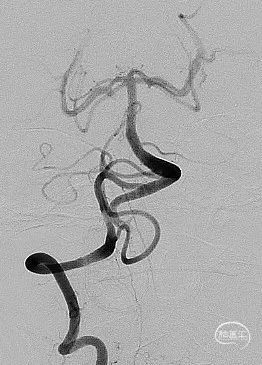

送入3.0mm*15mmNeuroform Atlas支架并释放,头端位于P3段,尾端位于P2段,释放后Atlas支架的Mark点显影良好。观察10分钟,P2段及远端血流仍通畅,未见血栓形成,遂结束手术。

术后即刻影像

治疗后工作位减影造影显示动脉瘤栓塞满意,载瘤动脉血流通畅。

动脉瘤为绝对宽颈,弹簧圈无法成篮,先半释放4.5mm*30mm Neuroform Atlas支架覆盖部分瘤颈,但弹簧圈仍突出于载瘤动脉,完全释放支架。头端位于颈内动脉末段,尾端位于眼段,支架顺利释放,Mark点显影良好。

治疗后工作位减影造影显示动脉瘤致密栓塞,子囊未显影载瘤动脉血流通畅。